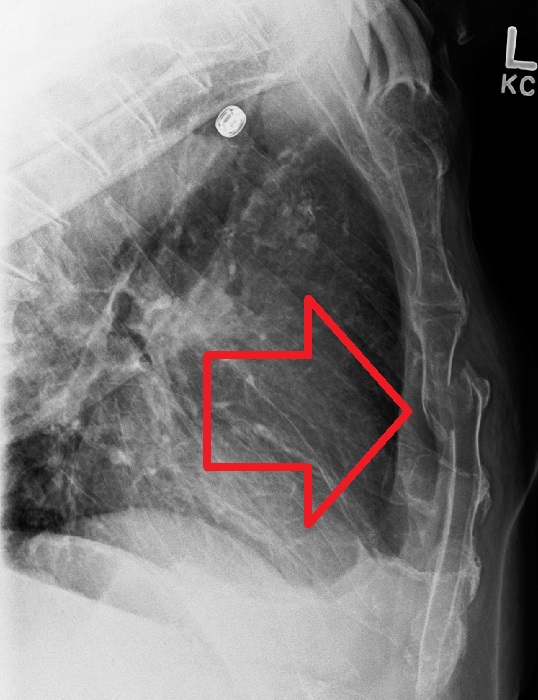

From www.svuhradiology.ie

Sternal fracture Radiology at St. Vincent's University Hospital How To Fix A Broken Sternum learn how to care for a broken sternum, which can take 3 months or longer to heal. chronic nonunion of sternal fractures is typically treated by osteosynthesis plating with or without. learn how to care for a broken sternum, a long, flat bone in the centre of the chest. learn about the common causes, symptoms and. How To Fix A Broken Sternum.